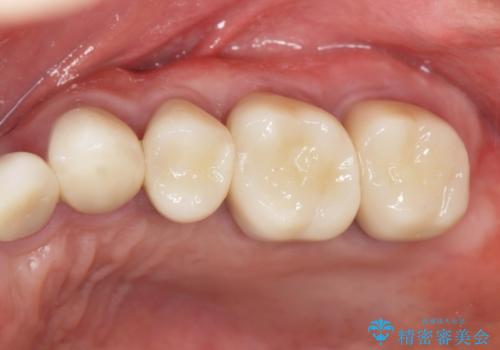

部分的な治療ではなく、全体的な治療を任せていただけたことで、清掃性の高く咬合関係の良い治療を行うことができました。

見た目の改善だけでなく、噛み合わせの仕上がりにも大変満足いただくことができました。